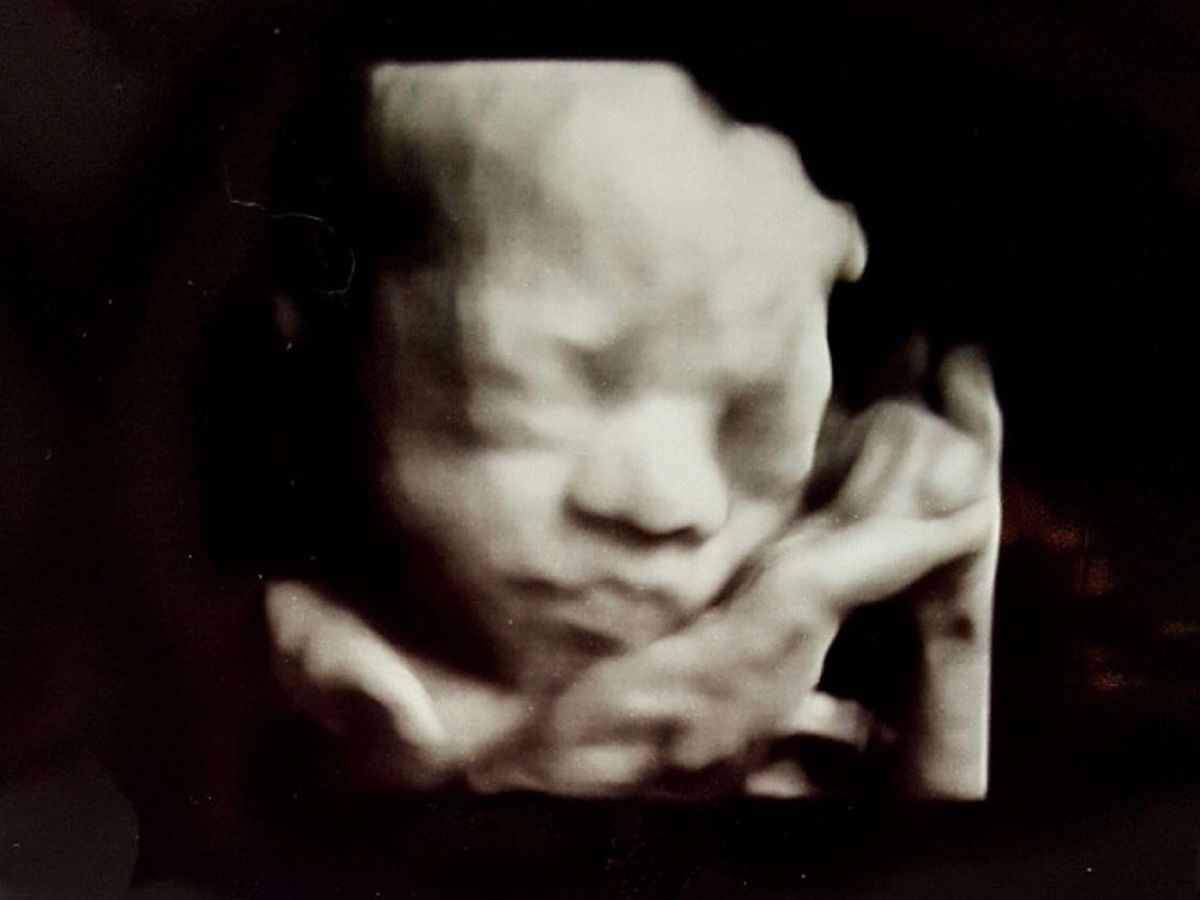

When Luis and Mercedes discovered they were expecting, they couldn’t wait to add a new member, Ellis, to the family. Unfortunately, after an ultrasound at week 22, something was revealed that they didn’t expect would happen again- another one of their children was diagnosed with Spina Bifida, as well as Hydrocephalus, and Arnold Chiara Malformation. Their oldest daughter, Bela, was diagnosed with Spina Bifida 9 years ago. In spite of her condition, Bela is a joy to her parents and all who know her. However, Luis and Mercedes know firsthand the challenges Ellis would face with Spina Bifida so their initial reaction was one of devastation. Thankfully God gave them a team of physicians at MUSC who informed them about a Fetoscopic Surgery which is performed at the Texas Children’s Fetal Center in Houston, Texas. This Fetoscopic surgery has only been performed 20+ times and is a minimally invasive, two-port procedure to repair spina bifida in-utero. It has been demonstrated that a fetal surgical repair leads to lower rates of hydrocephalus, decreases the need for a cerebrospinal fluid shunt, and improves leg function compared to standard after-birth repair of this condition. On average, the group treated before birth had better outcomes. As part of the treatment, Mercedes will be required to remain in Texas, away from her children and husband, for the rest of her term until Ellis is born. While many of the medical expenses will be covered for this procedure, other expenses will not. Mercedes will have housing, transportation and meal expenses as well as incidental costs during the next four months. She is also required to have an adult with her the entire stay so family and friends will have to travel out to Texas to stay with her. First and foremost please pray for Mercedes and Ellis as they go through the surgery and the remaining months of pregnancy. Secondly, if you are able to contribute to the Calderon’s expenses, please do so on this site. The family is grateful for your prayers and financial support. God bless.